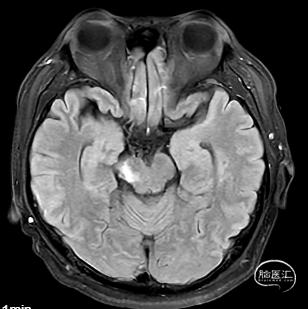

出院前复查

出院查体:神志清楚,GCS评分=E4V5M6=15分,检查合作,对答反应尚可,头颅五官无明显畸形,双侧瞳孔等大等圆,直径约3mm,双侧瞳孔光反射灵敏。双侧鼻唇沟对称,口角稍左偏,伸舌往右,双侧听力粗测正。右侧肢体肌力5级,肌张力正常,左侧下肢肌力3级,左上肢肌力2级,肌张力正常。双侧腱反射存在,生理反射灵敏,未引出克氏、布氏、巴氏征。